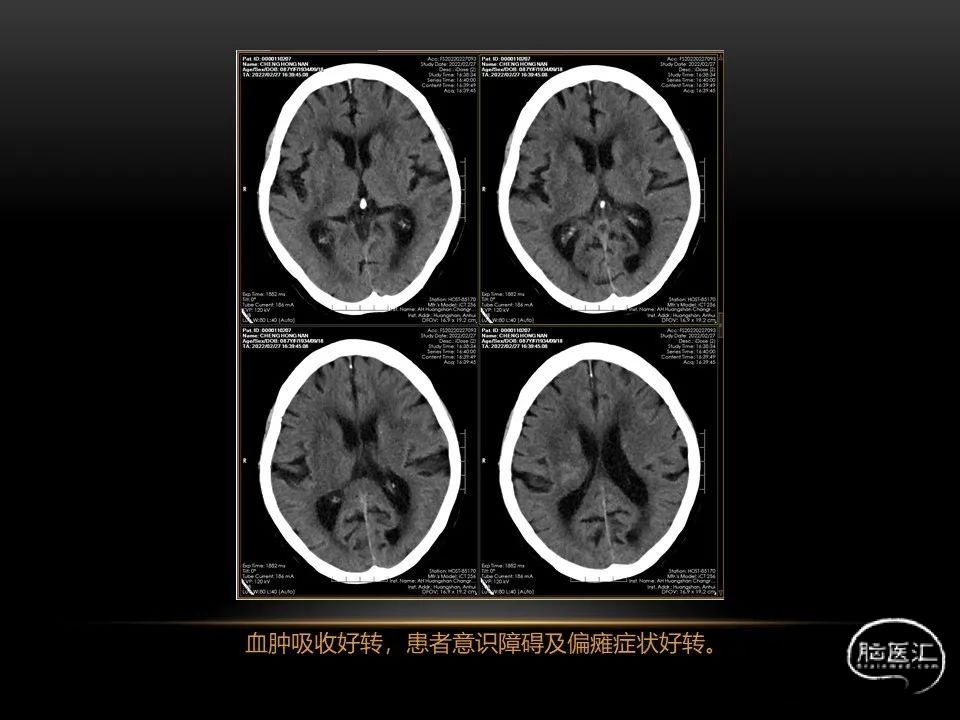

自发性脑出血临床上很常见,不同原因有特征性的出血部位。例如:基底节出血和丘脑出血大多是高血压性脑出血;脑叶出血,特别是多次复发的脑叶出血多见于老年人的脑血管淀粉样变。

自发性脑出血不仅仅累及内囊后肢才会出现偏瘫及偏身感觉障碍,病变累及大脑脚或辐射冠同样有可能有类似症状和体征。内囊、辐射冠、大脑脚等结构之间是延续的,只是不同区域不同名称而已。定位诊断需要对解剖结构概念清晰,读片准确辨认,灵活掌握。